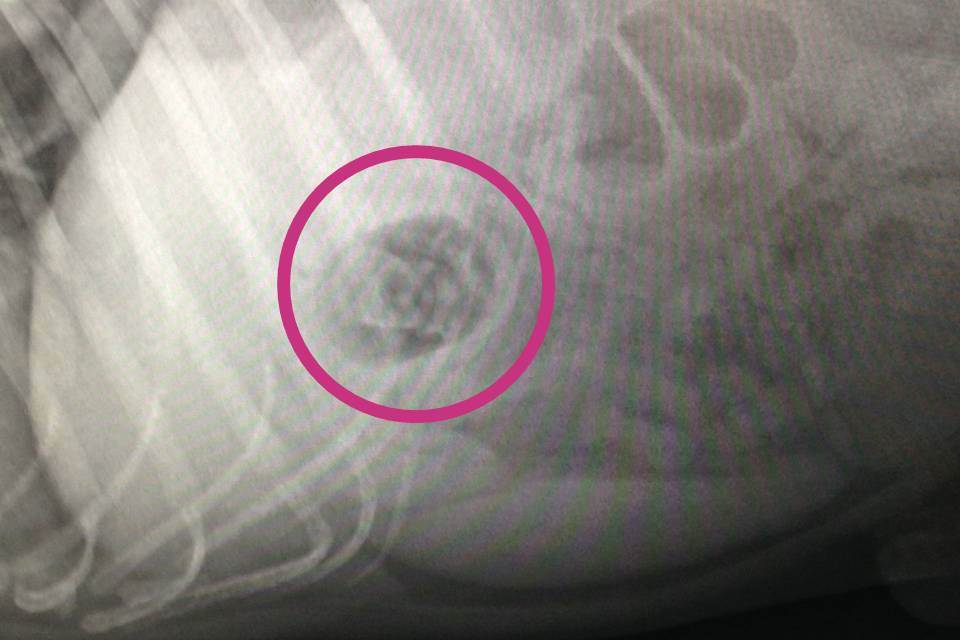

There were no prizes for guessing which toy was lurking inside Chase’s stomach after an x-ray revealed a Minion hiding within the plastic shell.

PDSA’s Head Nurse, Sarah Burt, said: “When Chase came to us you wouldn’t have known he was in danger because he was very alert and lively, but thankfully his owners had seen him swallow the egg and brought him to us. We took an x-ray which showed not only where the toy was in Chase’s body, but we could also make out roughly what the toy was.